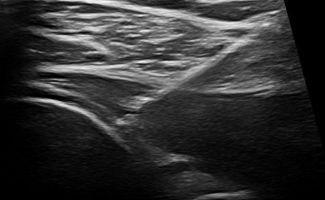

Κατά τη θεραπεία Barbotage γίνεται, με χορήγηση τοπικής αναισθησίας και υπό υπερηχογραφαγική καθοδήγηση, έκπλυση των ασβεστώσεων με φυσιολογικό ορό και έγχυση αντιφλεγμονώδους φαρμάκου στον υπακρωμιο-υποδελτοειδικό θύλακο του τένοντα.

Χάρη στην υπερηχογραφική καθοδήγηση, το Barbotage είναι μια αποτελεσματική και απόλυτα ασφαλής διαδικασία. Η χρήση του υπερήχου εξασφαλίζει τόσο την αποφυγή ζωτικών σημείων, όπως αγγείων και νεύρων, όσο και τη στοχευμένη έγχυση του θεραπευτικού μέσου ακριβώς στο σημείο των ασβεστώσεων, όπου χρειάζεται.